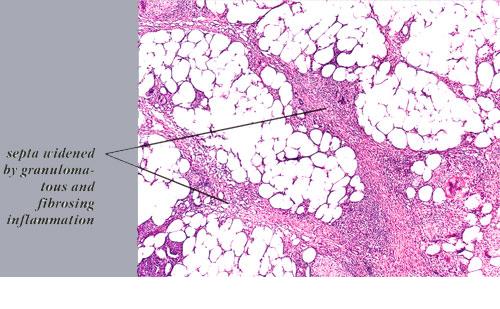

Histopathology. The histologic changes are present mainly in and near the septa of the subcutaneous tissue .

Later lesions of acute erythema nodosum show widening of the septa, often with fibrosis and with inflammation at the edges of the septa and involving the periphery of the fat lobules . Neutrophils usually are absent, and the vascular changes are less prominent than in early lesions. There are more macrophages in the infiltrate. Macrophages at the edges of the fat lobules show phagocytosis of lipid from damaged adipocytes, and the small droplets of lipid in their cytoplasm give them a "foam cell" appearance. Granulomas formed by macrophages, without lipid deposition, are more frequent

when late lesions are compared with early ones . The granulomas often are loosely formed with macrophages predominating in a focus with multinucleated giant cells. Occasionally, well-formed, discrete sarcoidal granulomas occur in small numbers in the septa. The multinucleated cells usually have an irregular distribution of the nuclei in the cytoplasm. The oldest lesions have septal widening and fibrosis with a decrease in all of the inflammatory cells.

In chronic erythema nodosum, the histologic findings are generally similar to those of the late stages of acute erythema nodosum. However, granulomas and lipogranulomas often are more pronounced in chronic erythema nodosum. There is vascular proliferation and thickening of the endothelium with extravasation of erythrocytes . In some instances, numerous well-formed granulomas can be found and consist of epithelioid macrophages and giant cells without caseous necrosis . Although significant degrees of vasculitis have been observed by some authors , others have found vascular changes to be slight or absent . The presence of thickened fibrotic septa with marked capillary proliferation and massive granulomatous reaction have led several authors to consider erythema nodosum migrans as an entity separate from the late lesions of acute erythema nodosum . Other authors consider all of these histologic patterns to be included within the spectrum of chronic erythema nodosum .